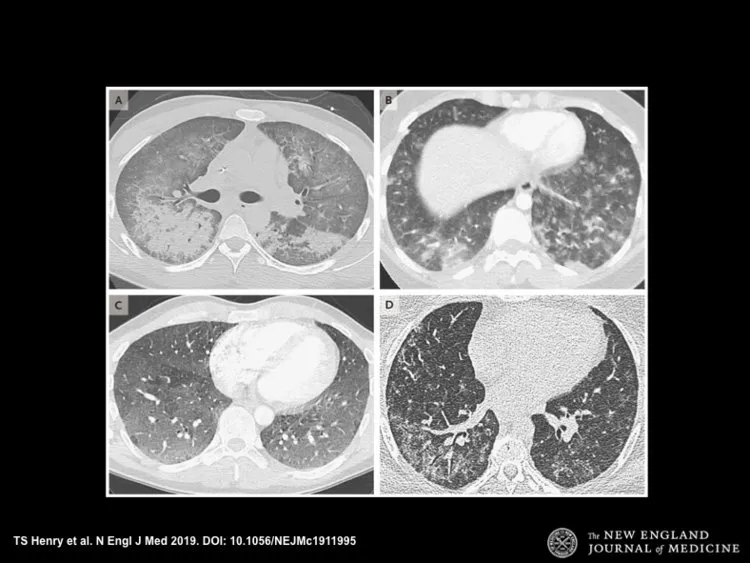

2019年9月美国电子烟肺炎案例

美国医生挖坟发现2019年9月美国电子烟肺炎的案例,经和中国武汉专家交流,确认就是“新冠肺炎”。

https://www.techspot.com/news/81793-deadly-vaping-related-lung-disease-claims-lives-four.html

注意报道的发布时间。